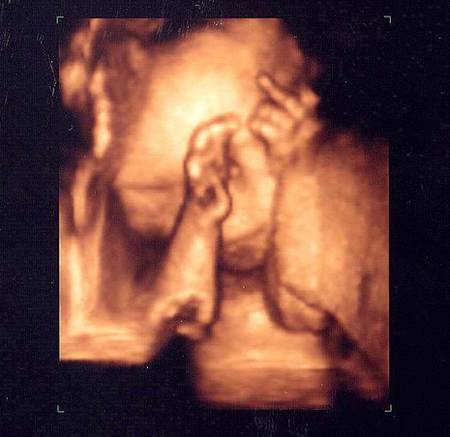

Nu mereu reușești să surprinzi atât de bine anumite imagini de ecograf. Tocmai de aceea, imaginile prezentate sunt foarte RARE!

De-a lungul timpului au fost surprinse mai multe imagini de ecograf cu adevărat uluitoare!

Iată mai jos 10 imagini de ecograf unice!